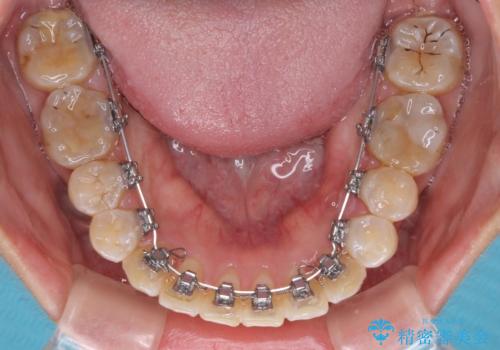

全く目立たないワイヤー矯正 上下裏側矯正

- リンガル

- 上下の前歯のでこぼこを気にして来院された患者様です。

職場の都合により、表側のワイヤー装置や着脱作業が頻繁なマウスピース矯正は困難とのことで、全く目立たない裏側矯正装置を用いて口元を整えることとしました。